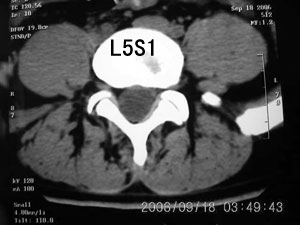

以下是引用守望可可西里在2006-9-18 21:29:00的发言:[br][br] 马尾肿瘤,密度较低,大部分似乎呈囊性变(看着很费眼),考虑室管膜瘤,建议mri。

以下是引用dyg在2006-9-18 22:27:00的发言:[br]正常脊髓.[br]分析:人的脊髓从枕大孔开始至腰1.2椎体为止,有2个生理膨大,分为颈膨大和腰膨大;该病人脊髓须然从腰段开始直至马尾似乎膨大,胆是与上段脊髓密度没有多大变化,所以我认为是正常膨大之延续;当然最好做ct增强或mri检查,排除肿瘤.

以下是引用飞虎在2006-9-18 20:18:00的发言:[br]部分椎管内密度不均且无ct值 故mri检查